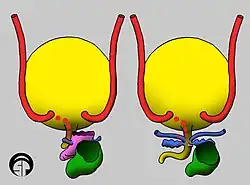

Nach seinem Eintritt in die Harnblasenwand verläuft der Harnleiter zunächst eine kurze Strecke innerhalb dieser Wand (intramural). Dieser intramurale Abschnitt ist 0,5 bis 1 cm lang,[10] nach anderen Angaben 1,5 bis 2 cm.[3] Dann durchbohrt er die Blasenschleimhaut und mündet mit der Harnleitermündung (Ostium ureteris) in das Innere der Harnblase. Die schlitzförmigen Harnleitermündungen sind klappenartig geschlossen, wenn durch sie kein Urin tritt.[3] Der Verlauf in der Blasenwand verhindert bei stärkerer Füllung der Harnblase einen Rückfluss des Urins zur Niere (vesikorenaler Reflux).[11] Die beiden Harnleitermündungen begrenzen mit der unpaaren Harnröhrenöffnung im Inneren der Blase das Harnblasendreieck (Trigonum vesicae).[12]

Die häufigste angeborene Fehlbildung beim Menschen, bedingt durch eine Störung der Embryonalentwicklung, ist die teilweise oder komplette Doppelanlage des Harnleiters (Ureter fissus bzw. Ureter duplex). Sie wird autosomal-dominant vererbt und tritt bei etwa 0,8 % der Menschen auf, in 20 bis 40 % der Fälle beidseitig. Diese Dopplung kann durch eine zusätzliche oder eine sich am Ursprung teilende Ureterknospe entstehen.[54] Die vollständige Dopplung zeigt sich häufig in vermehrten Harnwegsinfekten.[55] Sehr selten ist ein dreifach pro Seite angelegter Harnleiter, hier sind etwa 100 Fälle beim Menschen dokumentiert,[56] oder ein vierfacher Harnleiter.[57] In der alten Fachliteratur wurde auch das vollständige Fehlen (Agenesie) eines Harnleiters beschrieben.[58]

Eine weitere häufigere Fehlbildung ist die Harnleiterektopie, bei der die Mündung des Harnleiters nicht im Bereich des Harnblasendreiecks liegt. Sie entsteht wenn die Ureterknospe etwas höher als normal aus dem Urnierengang entspringt und sie dadurch weiter seitlich in den Sinus urogenitalis einbezogen wird. Mögliche Fehlmündungsstellen sind beim Mann Nebenhoden, Samenleiter, Spritzkanal und Bläschendrüse, bei der Frau tiefer am Blasenhals oder in Vagina, Gebärmutter oder Mastdarm.[59] Eine Harnleiterektopie tritt bei 0,05 % der Menschen auf, es sind vor allem Mädchen (80 %) betroffen, in etwa 10 % der Fälle tritt sie beidseitig auf. Da die Mündung stets hinter dem Blasenschließmuskel erfolgt, geht die Harnleiterektopie bei Mädchen immer mit unkontrollierbarem Harnträufeln (Harninkontinenz) einher.[60] Die Harnleiterektopie ist auch in der Tiermedizin von Bedeutung und für etwa 50 % der Fälle von Harnträufeln bei jungen Hunden verantwortlich.[61]

Der angeborene vesikorenale Reflux (VRR; auch vesiko-uretero-renaler Reflux, VUR) entsteht durch eine Harnleiterektopie oder durch einen verkürzten Verlauf des Harnleiters durch die Harnblasenwand (intramuraler Abschnitt).[11] Er tritt bei Kindern in einer Häufigkeit von 1 bis 2 % auf und wird zumeist im Zusammenhang mit Harnwegsinfekten entdeckt. Er ist für 10 % der Fälle einer vor der Geburt im Rahmen der Pränataldiagnostik festgestellten Hydronephrose verantwortlich.[66] Während der angeborene VVR zu 80 % Jungen betrifft, ist das Verhältnis beim erworbenen umgekehrt, hier ist das weibliche Geschlecht fünfmal häufiger betroffen.[67]

Die Ureterozele ist eine zystische Erweiterung des blasenseitigen Abschnitts des Harnleiters. Sie tritt bei einem von 4.000 Kindern auf, häufiger bei Mädchen und zumeist im Bereich des linken Harnleiters. Häufig liegt gleichzeitig eine Doppelniere vor. Die Ureterozele kann einen Rückstau des Urins und schließlich eine Wassersackniere verursachen.[70] Ein Megaureter, eine Erweiterung des Harnleiters auf mehr als 7 mm, tritt bei einer von 6.500 Lebendgeburten auf. Die Ursache ist unbekannt. Er kann infolge von Harnblasenerkrankungen mit Abflussstörung auch nach der Geburt entstehen. Der Megaureter zeigt sich durch Bauchschmerzen und Blut im Urin.[71]